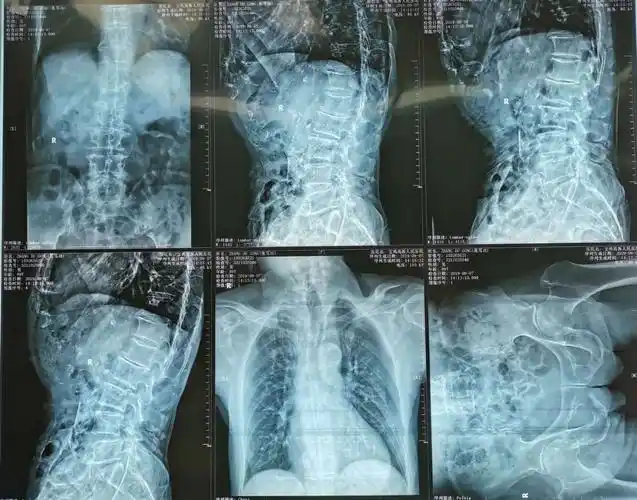

休息后疼痛没有减轻,来我院就诊,经查体拍片诊断为胸12椎体压缩性骨折

刚刚医院照的x光,有什么问题吗, 右上方那个圆形阴影是啥?